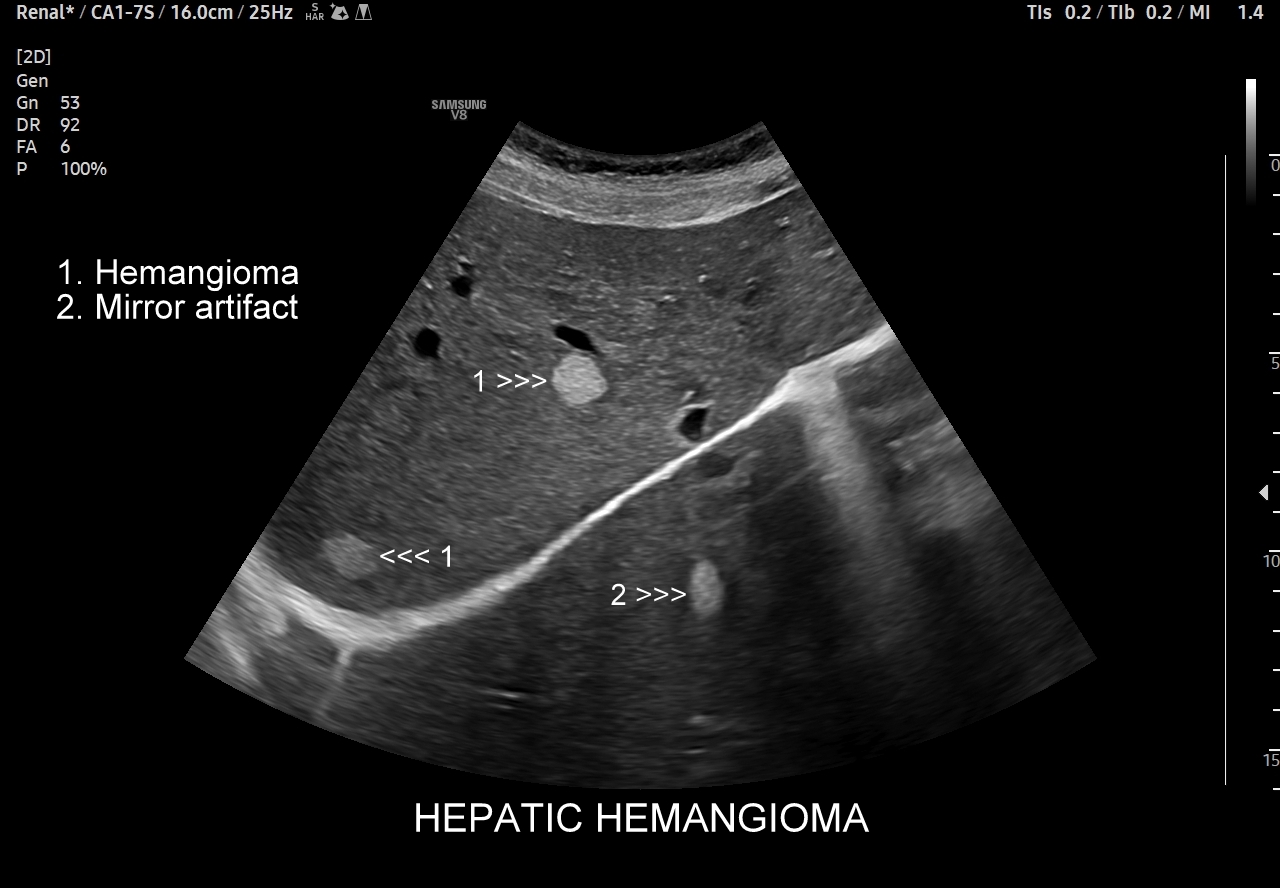

W badaniu USG w prezentacji B w niestłuszczonej wątrobie typowy naczyniak włośniczkowy lokalizuje się w pobliżu gałęzi żyły wątrobowej, a prezentuje się jako ostrookonturowana, hyperechogenna, jednorodna, krągła lub owalna zmiana ogniskowa. Ze względu na niską prędkość przepływu krwi i wynikające z tego ograniczenie detekcji w trybie color-Doppler w naczyniaku nie rejestruje się sygnału. Z kolei w trybie mikrounaczynienia (MVI / MVF) w zależności od czułości aparatury w naczyniaku można zaobserwować delikatny sygnał w postaci „poprószonego śniegu”.

Naczyniaki duże, tj. powyżej 2-3 cm, mogą mieć strukturę niejednorodną echogenicznie, w tym obszary hypoechogenne. Spotyka się także naczyniaki o charakterystyce normo- lub hypechogenicznej, w szczególności w wątrobie stłuszczonej. Z powyższych względów należy mieć na uwadze i zapamiętać, że badanie USG w podstawowym trybie B nie jest wystarczające do postawienia rozpoznania naczyniaka wątroby. W ramach obrazowej diagnostyki różnicowej najbardziej pomocnym jest badanie USG z kontrastem (CEUS), w którym to naczyniak wątroby posiada charakterystyczny wzorzec wypełnienia.